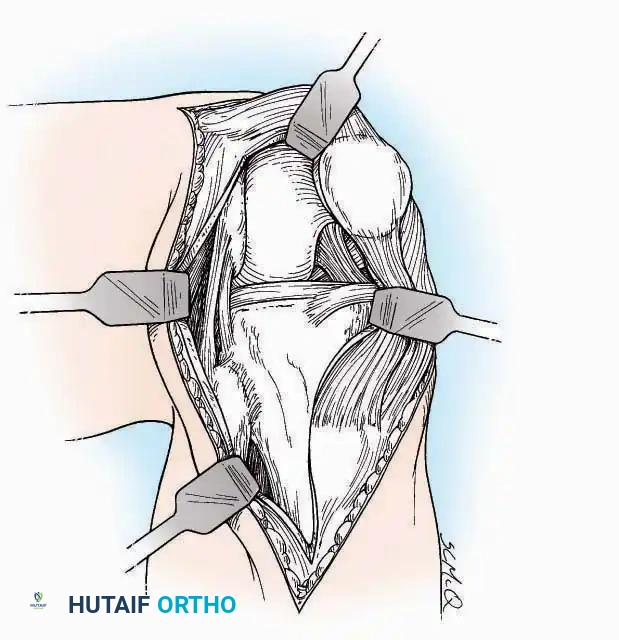

Anterior Approach

Indications: Total ankle arthroplasty (TAA), anterior ankle arthrodesis, and excision of anterior tibial/talar osteophytes (anterior impingement).

Surgical Technique:

* Incision: Make a 10 to 15 cm longitudinal incision over the anterior aspect of the ankle, centered exactly midway between the medial and lateral malleoli.

* Superficial Dissection: Incise the superficial fascia. Identify and protect the superficial peroneal nerve branches laterally and the saphenous nerve medially.

* Internervous Plane: The deep dissection exploits the plane between the Extensor Hallucis Longus (EHL) tendon (innervated by the deep peroneal nerve) and the Extensor Digitorum Longus (EDL) tendons (also innervated by the deep peroneal nerve).

* Neurovascular Bundle: Incise the extensor retinaculum. Carefully identify the anterior tibial artery and the deep peroneal nerve, which typically lie between the EHL and EDL, or directly deep to the EHL. Retract the neurovascular bundle laterally with the EDL, or medially with the EHL, depending on the specific anatomical variant encountered (lateral retraction is most common).

* Capsulotomy: Incise the anterior joint capsule longitudinally. Elevate the capsule subperiosteally from the anterior tibia and the talar neck to expose the entire tibiotalar articulation.